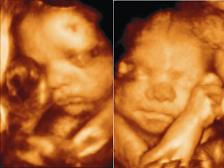

Hát örömmel jelentem, hogy meg volt a 12+3 napon az UH vizsgálatom. ÉS mindent rendben találtak!!!! :D

A CRL 67mm, a BDP 22mm, a tarkóredő 1,6 és van orrcsontja is.

Elvileg aznap este még megyünk 4D-s ultrahangra is, feltéve ha odaérünk. A pármon szeretne elmenni mindenáron, és akkor megbeszéltük, hogy most meg a terhesség vége felé elmegyünk még egyszer aztán ennyi.

Elhiszem, hogy megnyugodtál! Egyetértek Flocikával, sztem is korai még ilyenkor a 4d, főleg, hogy minden rendben van a babóval. Mi a 25. héten voltunk, az volt a csúcs!!! Apuci még elvitt a 35. héten is, mert annyira élvezte, de ott már olyan nagy volt Máté, hogy kb csak a feje fért be a képbe :lol:

Hétfőn elmentem a Védőnőhöz (Pocsai Jánosné), aki nagyon aranyos, csak egy kicst lassúnak tűnt, főleg annak a fényében, hogy 6-tól rendel én már 1/2 6-ra ott voltam, hogy biztosan első legyek. Egy órát voltam nála, amíg felvette az adataimat, végülis semmi más nem történt. Viszont 1/4 nyolcra volt a rendelés a 4d uh-n.Mivel a párom mindenképpen szerette volna látni. Ja és az igaz, hogy nem olyan élvehető a kép, mert pl. Az ujjacsáit nem láttam tisztán, de az lehet, hogy a könnytől volt. Viszont az, hogy egyfolytában mozgott, ugy kapott a kezecskéjével a levegőben, mint a kismacska szokott a lógó madzagdarab után. A szája egyfolytában járt, kinyitotta összecsukta. Szerintünk még mosolygott is.MEg olyan kirdásokat végzett a lábaival, hogy ha nagykorában is ezt csinálja, nekem ki fog lyukadni az oldalam. :)

Nem tudom, hogy minden kismagzat ilyen virgonc-e ebben a korban, de ő ugrált, a fenekét mutatta, stb. Ja és az tetszett a legjobban, hogy hátravetette többszür is magát, mint egy kisbaba. :)

Győzőtt bennünk a kíváncsiság, és mégis elmentünk 4d uh-ra. Hát az nagy élmény volt. Közben rájöttem, hogy erről már írtam fent. Sikerült már képeket is kivágnom a DVD-ről, ha érdekel megmutatom, bár tényleg nem olyan éles a sok nevetéstől, amit a vizsgálat közben nem tudtam visszatartani.